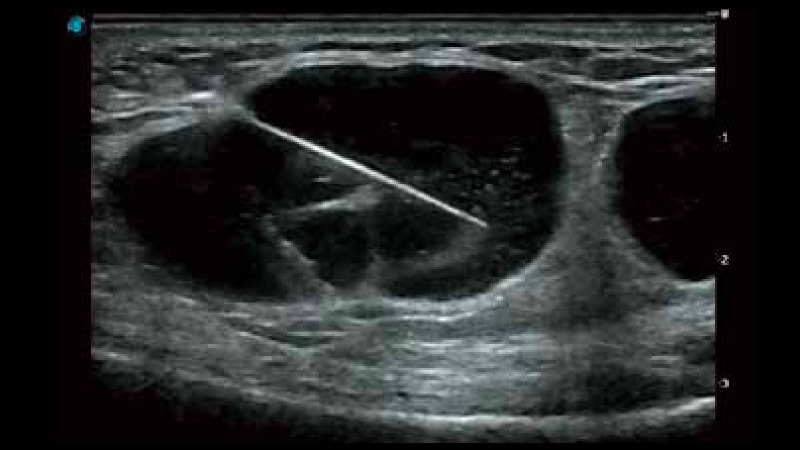

穿刺增强

临床图像